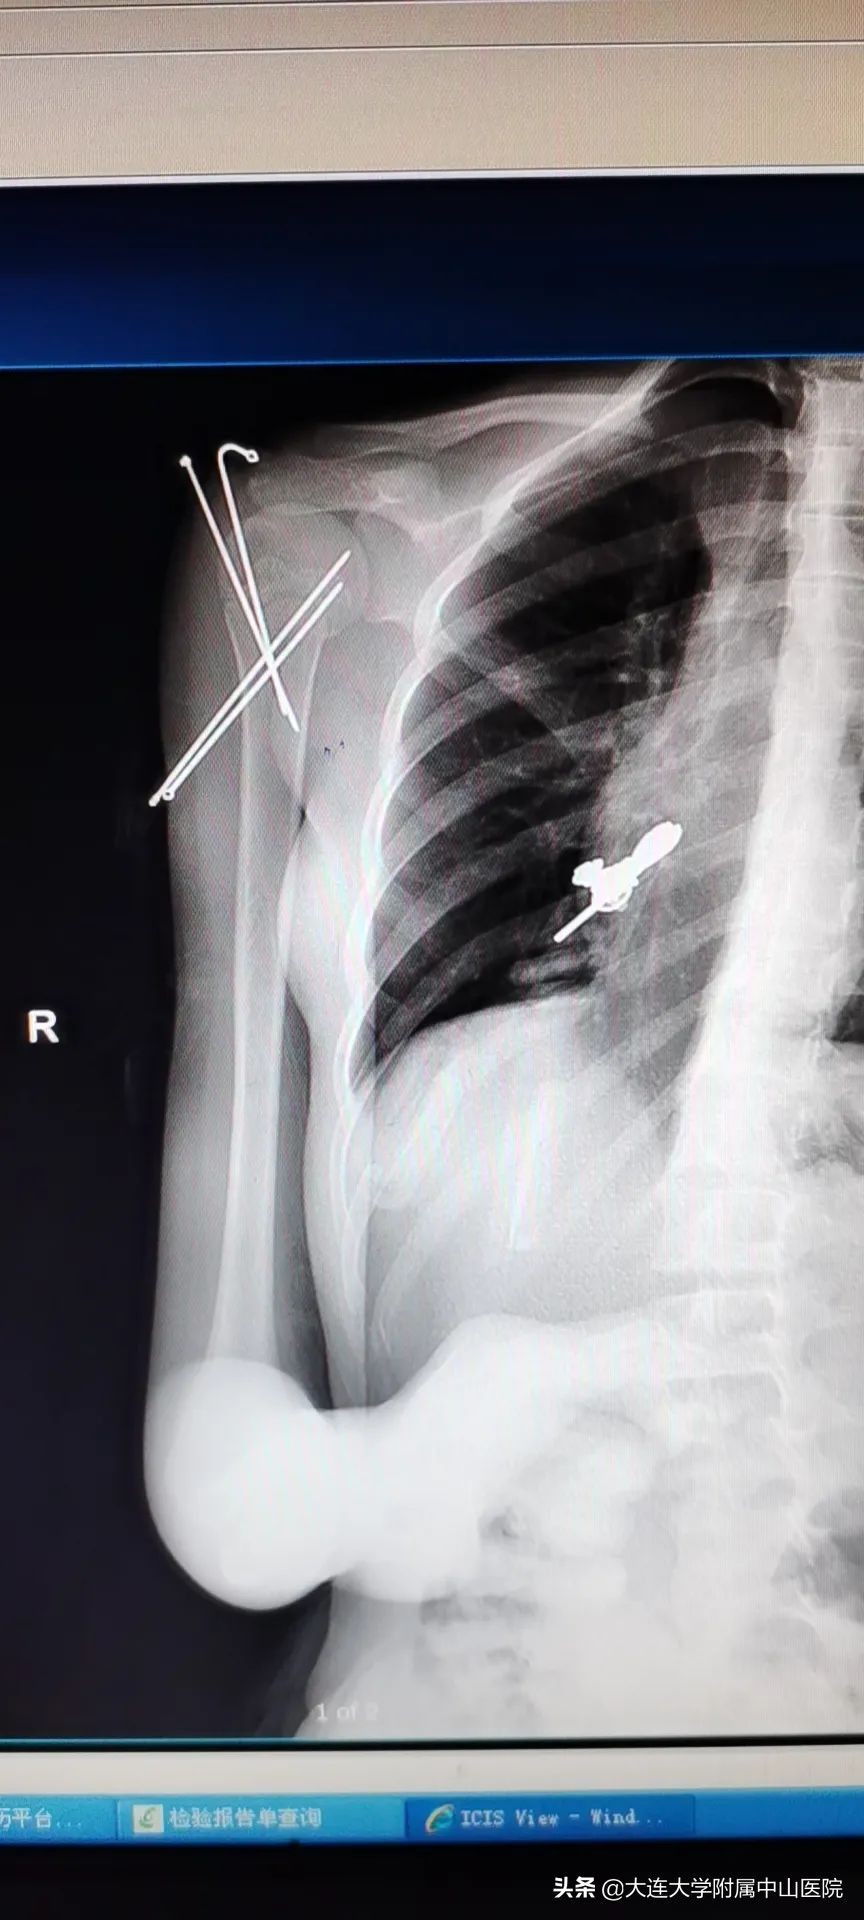

近日,11岁的小姑娘因摔伤致右肱骨近端骨骺骨折,外院就诊,医生建议切开复位做内固定手术,家长想想未来女儿胳膊上留有一道长长的刀疤,就心如刀割。经别人推荐,大连大学附属中山医院造船分部小儿骨科,无痛手法复位和微创手术技术精湛,于是便慕名而来。马晓伟主任第一时间接诊了患儿,小儿骨科医疗团队经过认真分析讨论,征求患儿及家属同意后,在全麻下为小姑娘施行了微创手术治疗。术后创面只有四个针眼,骨折复位效果良好,家长非常满意。

马晓伟主任介绍,儿童不是成人的简单缩影,他们有其自身特点,比如愈合快、治疗周期短、手术创面外形要求高等,这就给我们的诊疗提出了更高的要求,“简单内固定,有效外固定”是其治疗原则。闭合骨折,我们尽量争取在无创手法复位后给予可靠固定,尽量避免手术。如果无创手法复位不成功或者骨折端不稳定,我们也首选微创手术,用最小的创伤、最合适的治疗方案取得最佳的治疗效果。对待每一个小儿患者,我们都是根据病情为其制订最合适的、创伤最小的个体化治疗方案,最大限度地缩短治疗周期,让孩子们能早日回到正常的学习和生活中。